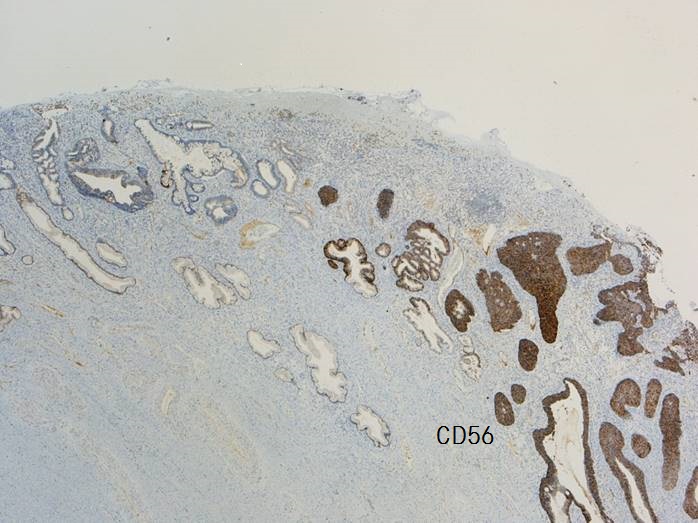

腺管構造や充実性胞巣構造を形成し増生していた。充実性増生を示す成分はN/C比や核分裂像が目立ち、免疫染色ではsynaptophysin、chromogranin A、CD56が陽性であり神経内分泌分化が示唆された。以上の所見より、神経内分泌癌成分を伴う腺癌と診断された。面積的には腺癌成分が8割で神経内分泌癌成分は2割であった。腺癌成分で微小浸潤がみられたが神経内分泌癌成分はin situであった。

腺管構造や充実性胞巣構造を形成し増生していた。充実性増生を示す成分はN/C比や核分裂像が目立ち、免疫染色ではsynaptophysin、chromogranin A、CD56が陽性であり神経内分泌分化が示唆された。以上の所見より、神経内分泌癌成分を伴う腺癌と診断された。面積的には腺癌成分が8割で神経内分泌癌成分は2割であった。腺癌成分で微小浸潤がみられたが神経内分泌癌成分はin situであった。